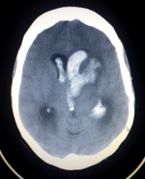

Intracranial Hemorrhage

- Intra-axial

- Hemorrhagic stroke (Spontaneous intracerebral hemorrhage)

- Traumatic intracerebral hemorrhage

- Extra-axial

- Epidural hemorrhage

- Subdural hemorrhage

- Subarachnoid hemorrhage (aneurysmal intracranial hemorrhage)